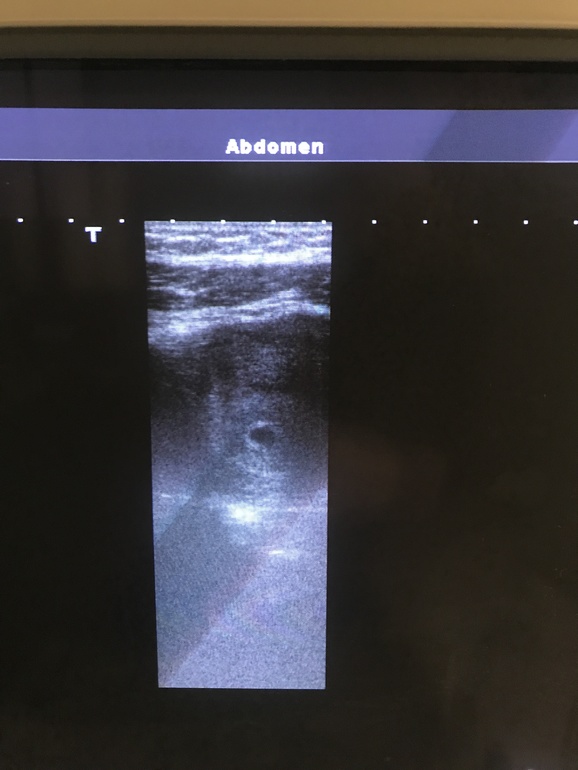

По поводу снимка узи

УЗИ, КТГ, доплерЯ тут пересматриваю узи своё и вот что мне интересно. Я сейчас скину 3 фотки. Оригинал и 2 с обведёнными кругами. Я присмотрелась и такое чувство, будто бы там как перегородка что-ли. Ну в общем посмотрите. Вот плодное яйцо более темное и сбоку как что-то круглое, но не такое тёмное. Что это?))